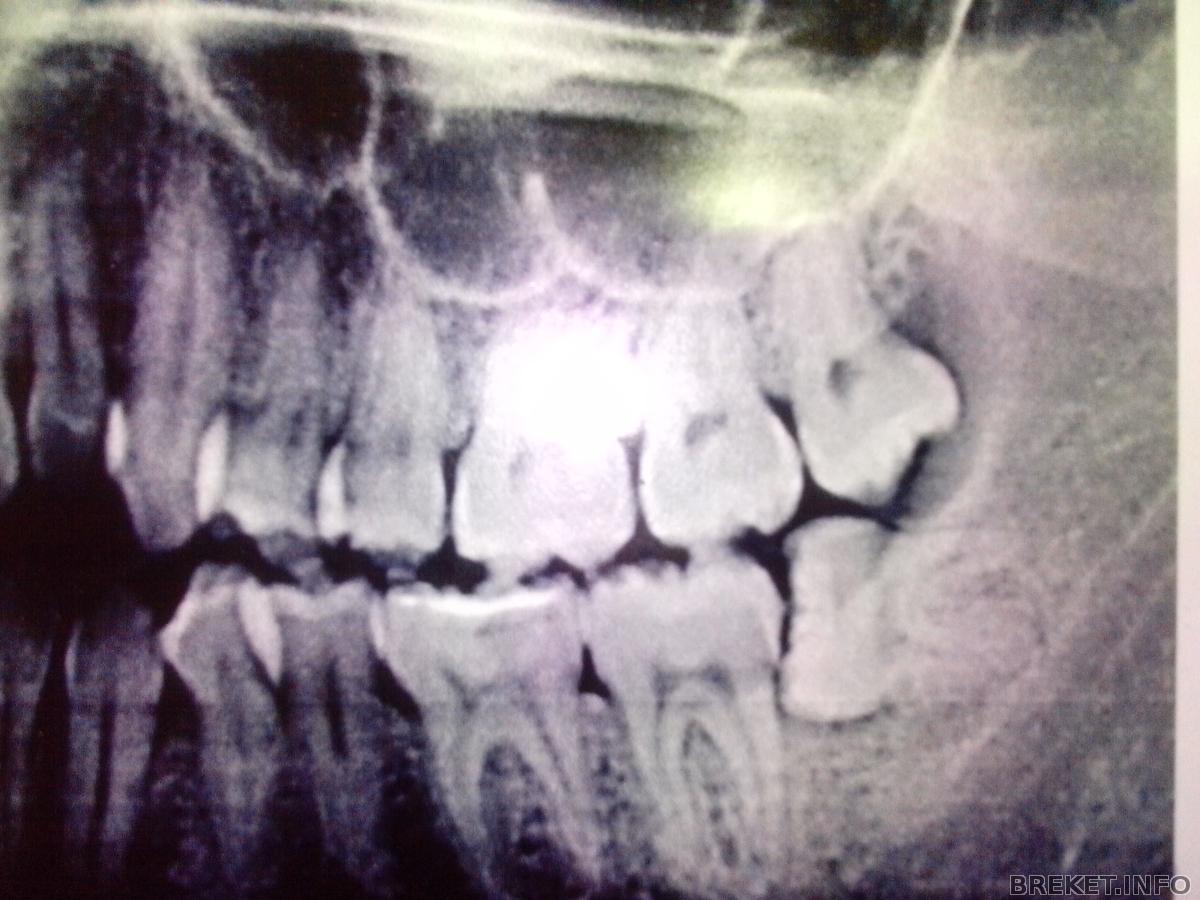

Откопала вот старый снимок

Нижнего лежачего безобразия уже нет, конечно, а вот верхний - тот самый, мой мучитель.